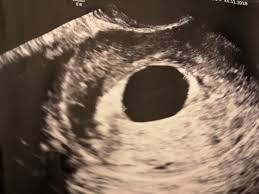

Can a blighted ovum cause an early miscarriage? Nov 10, 2020 · how long can you carry a blighted ovum? Many women need support and time to grieve. It's also called anembryonic pregnancy or empty sac. What to do with a blighted ovum pregnancy? The placenta and sac still give off pregnancy hormones. Dec 13, 2017 · the sonogram will show the placenta and empty embryonic sac. While you can technically get pregnant again as soon as your periods return, we recommend that you wait for about three months to fully heal after a miscarriage.

Dec 13, 2017 · the sonogram will show the placenta and empty embryonic sac. While a blighted ovum leads to loss of pregnancy, most women tend to have healthy pregnancies and babies subsequently. What are the treatment options? Nov 10, 2020 · how long can you carry a blighted ovum? While you can technically get pregnant again as soon as your periods return, we recommend that you wait for about three months to fully heal after a miscarriage. A miscarriage is when a pregnancy ends on its own within the first 20 weeks. How long can a blighted ovum pregnancy last? These cause a pregnancy test to show positive, and can give you symptoms of pregnancy. You have a placenta and a gestational sac, but the embryo doesn't grow. Your body understands the pregnancy is not developing properly and starts to shed blood and tissue from the uterus. It's also called anembryonic pregnancy or empty sac. Blighted ovum is a type of early pregnancy loss. Experiencing a miscarriage for any reason is painful.